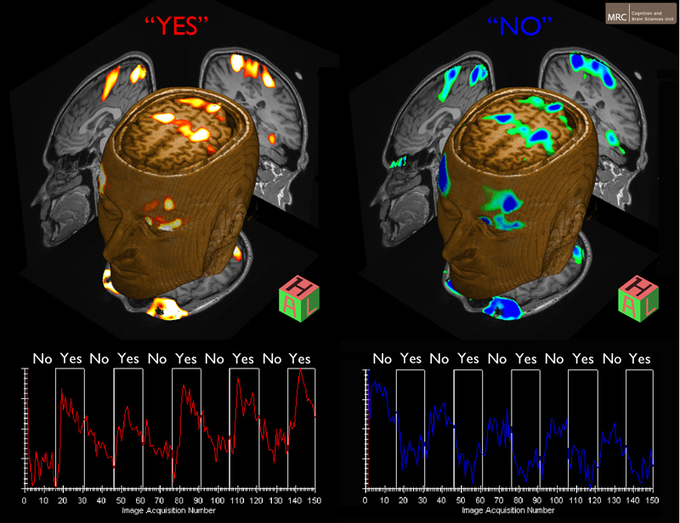

Comunicación en vegetativo. Fuente: Universidad de Cambridge.

Owen y sus colaboradores utilizaron entonces una técnica de escaneo cerebral denominada exploración por resonancia magnética funcional (fMRI) que les permitió registrar la actividad cerebral del joven mientras éste contestaba “sí” o “no” a preguntas como “¿tú padre se llama Thomas?”

Dado que las señales cerebrales asociadas al “sí” o al “no” son complejas y muy similares, los científicos pidieron al joven que imaginara que jugaba al tenis cuando quería decir “sí” y que paseaba por algún lugar cuando quería decir “no”.

Pensar en los movimientos del tenis pone en marcha regiones del cerebro relacionadas con las actividades espaciales, mientras que pensar que se está dando un paseo por cualquier sitio activa regiones cerebrales vinculadas con la orientación.

Gracias a este cambio en sus pensamientos, y a su reflejo diverso en la actividad neuronal consecuente, los científicos pudieron interpretar las respuestas del paciente a las preguntas que se le realizaron.

Owen y sus colaboradores utilizaron entonces una técnica de escaneo cerebral denominada exploración por resonancia magnética funcional (fMRI) que les permitió registrar la actividad cerebral del joven mientras éste contestaba “sí” o “no” a preguntas como “¿tú padre se llama Thomas?”

Dado que las señales cerebrales asociadas al “sí” o al “no” son complejas y muy similares, los científicos pidieron al joven que imaginara que jugaba al tenis cuando quería decir “sí” y que paseaba por algún lugar cuando quería decir “no”.

Pensar en los movimientos del tenis pone en marcha regiones del cerebro relacionadas con las actividades espaciales, mientras que pensar que se está dando un paseo por cualquier sitio activa regiones cerebrales vinculadas con la orientación.

Gracias a este cambio en sus pensamientos, y a su reflejo diverso en la actividad neuronal consecuente, los científicos pudieron interpretar las respuestas del paciente a las preguntas que se le realizaron.